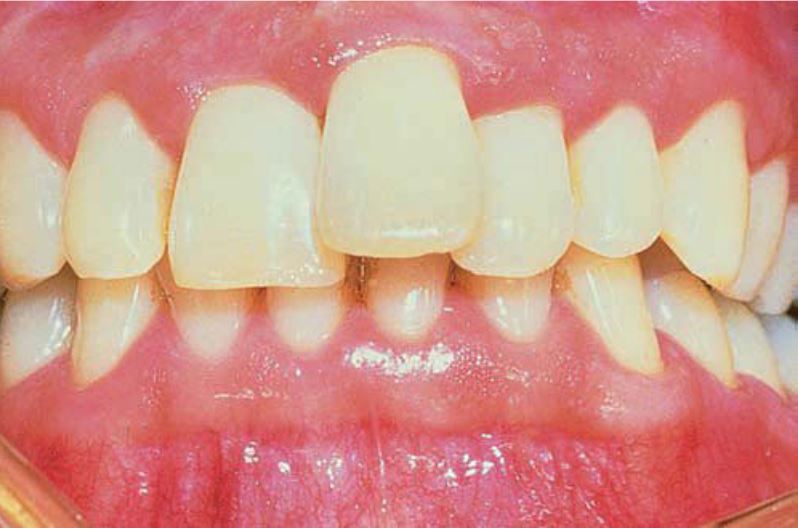

Chân răng gấp khúc

Chân răng bị gấp khúc, tạo góc >20 độ so với thân răng. Chân răng gấp khúc hay gặp khi răng chen chúc, chấn thương, tổn thương xương răng kế bên hoặc do lực chỉnh nha. Chân răng có thể phân kì khỏi thân răng theo tất cả các hướng, nhưng thường gặp nhất là theo hướng xa, xa ngoài hoặc xa trong.

Khi chân răng phân kì về phía ngoài hoặc trong thì trên X quang sẽ có hình ảnh “mắt bò”, với điểm trung tâm là ống tủy.

Chân răng gấp khúc gây khó khăn cho việc điều trị tủy, nhổ răng và chỉnh nha.